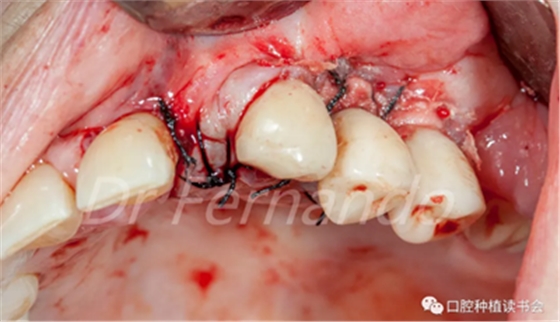

在骨粉上方覆蓋 Osgide? 可吸收膠原膜(Curasan?-科盧森) ,用絲線嚴密關(guān)閉傷口(圖 22 )

圖22 植骨區(qū)覆蓋可吸收膠原膜,關(guān)閉創(chuàng)口